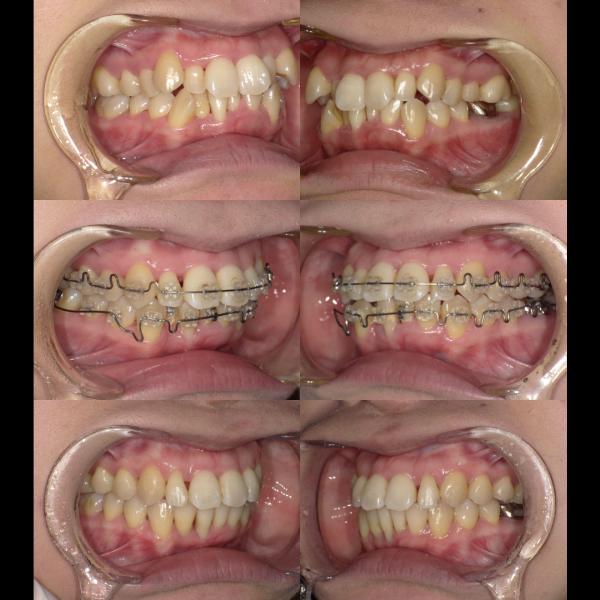

現在、歯列不正になる原因は、下顎の位置関係、歯の傾きなど様々な要因があることがわかっています。

そういった様々な要因を取り除くことで、従来、小臼歯(4番、5番)を抜歯しなければ治療できない症例でも、非抜歯で治療可能となってきているのです。

機能的に小臼歯は非常に大切な歯であることから、最大限小臼歯を抜歯せずに治療できる治療方針を考えます。

また、下顎の位置関係、歯の傾きなどの原因を新素材ゴムメタルワイヤーで治療を行うことでほとんどの症例で小臼歯を抜歯しなくても治療可能になってきています。